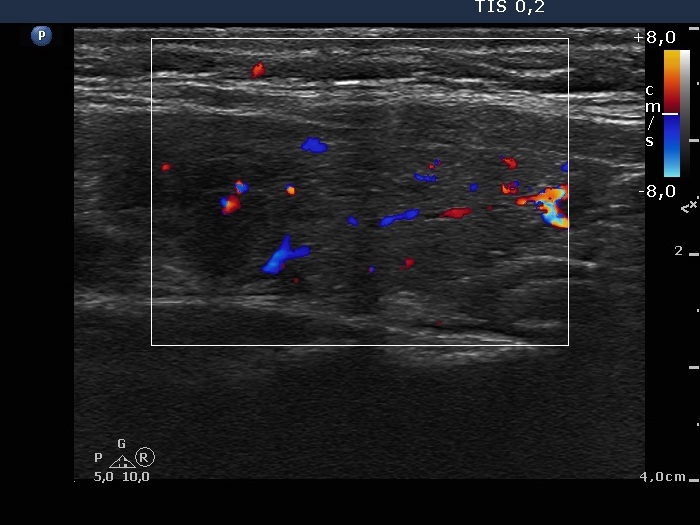

Left lobe, longitudinal scan, color Doppler mode. The vascularization is not specific.